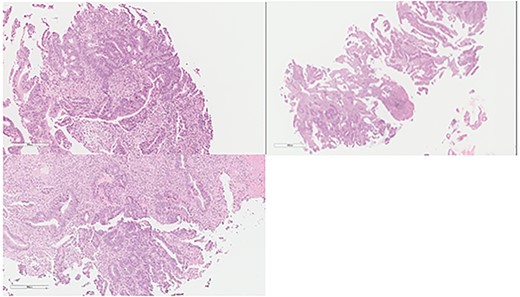

An otherwise healthy 73-year-old male, presented with rectal bleeding 6 months back. Colonoscopy revealed a sigmoid colon mass about 25 cm from the anal verge extending 10 cm proximally and a biopsy confirmed invasive adenocarcinoma (Fig. 1) Computed tomography of the abdomen and pelvis revealed a circumferential wall thickening involving the distal colon/proximal sigmoid colon spanning for 6 cm with maximum thickness of 2.3 cm, and it was also associated with surrounding fat stranding and multiple regional lymph nodes. Liver lesions were described as ill-defined hypodense lesions in two segments. The first lesion was seen in segment 7 measuring 6 × 7.5 cm and the other was seen in segment 5 measuring 6 × 3 cm (Fig. 2). Furthermore, chest CT showed no lung metastasis and a carcinoembryonic antigen level of 24.8. Eventually, a diagnosis of metastatic sigmoid adenocarcinoma with liver lesions was made. The multidisciplinary team decided to start the patient on Nac and then the case was reassessed for further resection. After completing five cycles FOLFOX, a CT of chest, abdomen and pelvis was performed for evaluating the response. The primary descending colon tumor demonstrated reduction in bulk with persistent serosal irregularity and no definitive regional lymphadenopathy was detected. The hepatic lesions revealed a partial response; in segment 7, the lesion is currently measuring 3.9 cm and in segment 5, the lesion measures 2.7 cm. Partial response to therapy was noted by a 41% reduction in sum tumor burden as per RECIST criteria (Fig. 3). The clinical tumor node metastasis classification post chemo was calculated to be T2N0M1 for descending colon cancer along with a CEA of <1.7. Despite not adding a biological agent with the systemic therapy which is the standard protocol in metastatic CRC, the patient achieved a remarkable reduction in tumor burden. The patient underwent a laparotomy with a low anterior resection of the rectum and anastomosis, synchronous resection of segments 6 and 8 of the liver along with a right-sided diaphragmatic stripping.

Colon: status of pre NAC: colonic mucosa with an infiltrative malignancy formed by tubules and gland of epithelial cells with high nucleus to cytoplasm ratio. The cells are large with frequent mitosis.

Colon: status of post NAC with complete response. Mucosal ulcer, fibrosis, calcification and histolytic collection with no tumor cells.